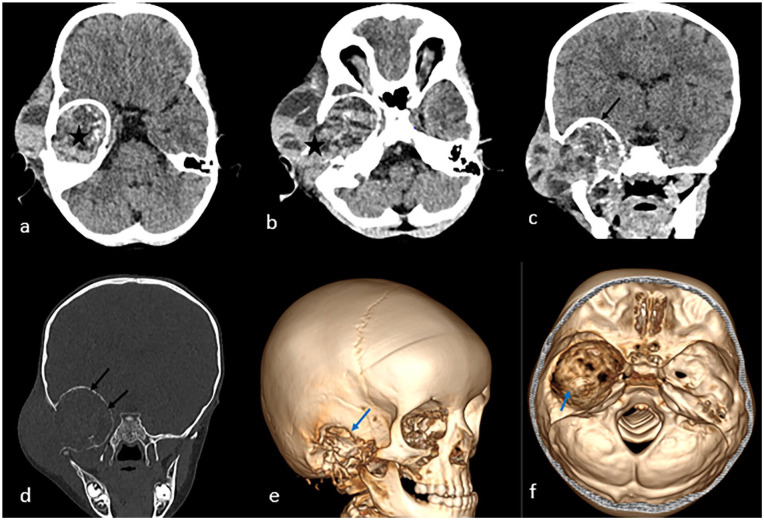

Infantile myofibromatosis is a proliferative disorder occurring during infancy and early childhood, marked by the development of nodular or diffuse lesions consisting of various mesenchymal elements. Intracranial involvement is infrequently reported. Here, we present the case of a 3-year-old girl exhibiting a rare manifestation of IM with intracranial parenchymal involvement, displaying a histological pattern documented in existing literature on patients with infantile myofibromatosis. Subsequent MRI follow-up revealed no signs of recurrence.